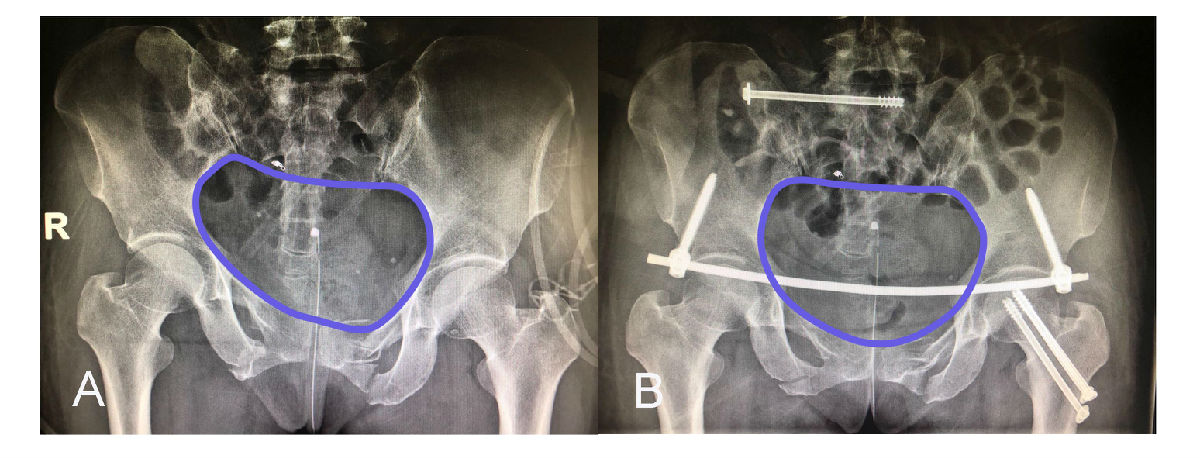

A 術(shù)前骨盆平片提示骨盆骨折后骨盆環(huán)移位變形;B 經(jīng)微創(chuàng)治療后,骨盆骨折獲得良好的復(fù)位,骨盆環(huán)恢復(fù)解剖形態(tài)。